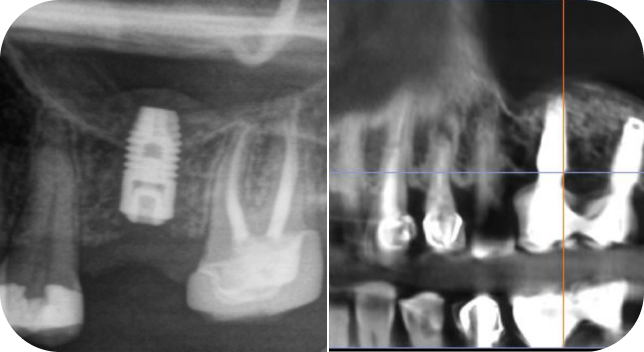

Клинические кейсы — это то, на чем базируется все обучение с конкретными пояснениями.

30+ клинический кейсов